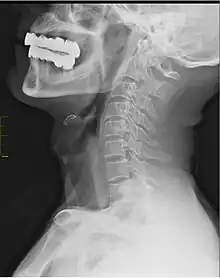

In human anatomy, arcuate foramen, also known as ponticulus posticus (Latin for "little posterior bridge") or Kimmerle's anomaly,[1] refers to a bony bridge on the atlas (C1 vertebra) that covers the groove for the vertebral artery. It is a common anatomical variation and estimated to occur in approximately 3-15% of the population.[2][3][4] It occurs in females more commonly than males.[3][5] The ponticulus posticus is created through ossification of the posterior atlantooccipital ligament.

The presence of arcuate foramen is associated with headache, musculoskeletal pain[3] and vertebrobasilar stroke.[2]